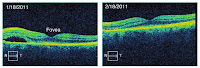

3. Figure 14.16. Color! This optical coherence tomogram of the retina was supplied by Kirk Morgan. A few figures in IPMB go beyond black and white, but this is the only one in glorious full color.